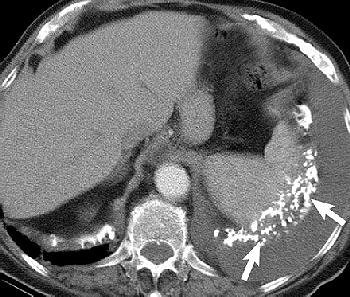

Sonography has no value in the detection of mesothelioma, but it can offer vital information for confirming and fine-tuning the initial diagnosis made with other modalities. Ultrasound is particularly useful for identifying disease changes to the chest wall, diaphragm, or upper chest aperture, explained Dr. Felix Herth from the department of pneumology at the Thoraxklinik in Heidelberg, Germany.

Herth recommended using a highly soluble transducer (5 MHz) to look at pathological findings in the chest wall of mesothelioma patients. In advance stages of the disease, tumor infiltration of the lung tissue will appear as echo-poor, oblong structures along the ventilated lung. Pleural metastases are also echo-poor, or moderately echo-close, and present as roundish, small, knotty, or laminar processes with irregular delimitation.

| A Brustwand echocardiogram depicting infiltrating carcinoma. |

"Pleural mesothelioma presents sonographically as an irregularly limited, echo-poor, knotty, or planar widening along the pleura," Herth wrote in Lung Cancer. "An increase in the pleural thickness, however, suggests the likelihood of malignancy. A widening of the pleura of more than 1 cm is considered highly indicative of the presence of malignant tumor" (August 2004, Vol. 45:1 supplement, pp. S63-67).

Ultrasound can also aid in lung puncture technique, either as guidance for needle placement or for visualization of the entire procedure. Hertz recommended ultrasound over CT for these procedures as it enables continued monitoring, costs less, and does not pose a radiation risk.